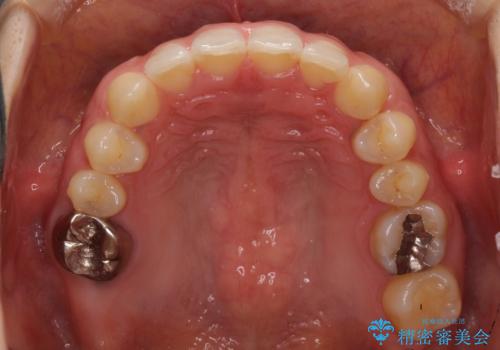

- 前歯の隙間と奥歯の目立つ銀歯を気にして来院された患者様です。

インビザラインにより下顎前歯の隙間を閉じるとともに、奥歯の咬み合わせを改善させることとしました。

矯正治療後には、銀歯のクラウンをセラミッククラウンへ替える補綴治療を行うこととしました。

左右奥歯の咬み合わせを変更させる必要があったため、治療期間は長くなることが予想されました。

1日22時間以上の装着時間をしっかりと守ってくださったので、順調に治療を進めることができました。